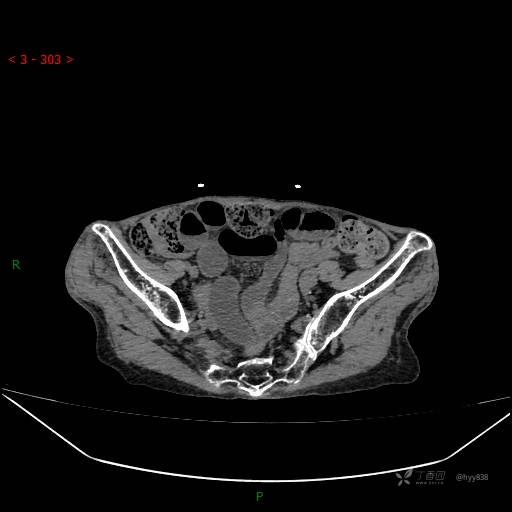

腹部CT平扫